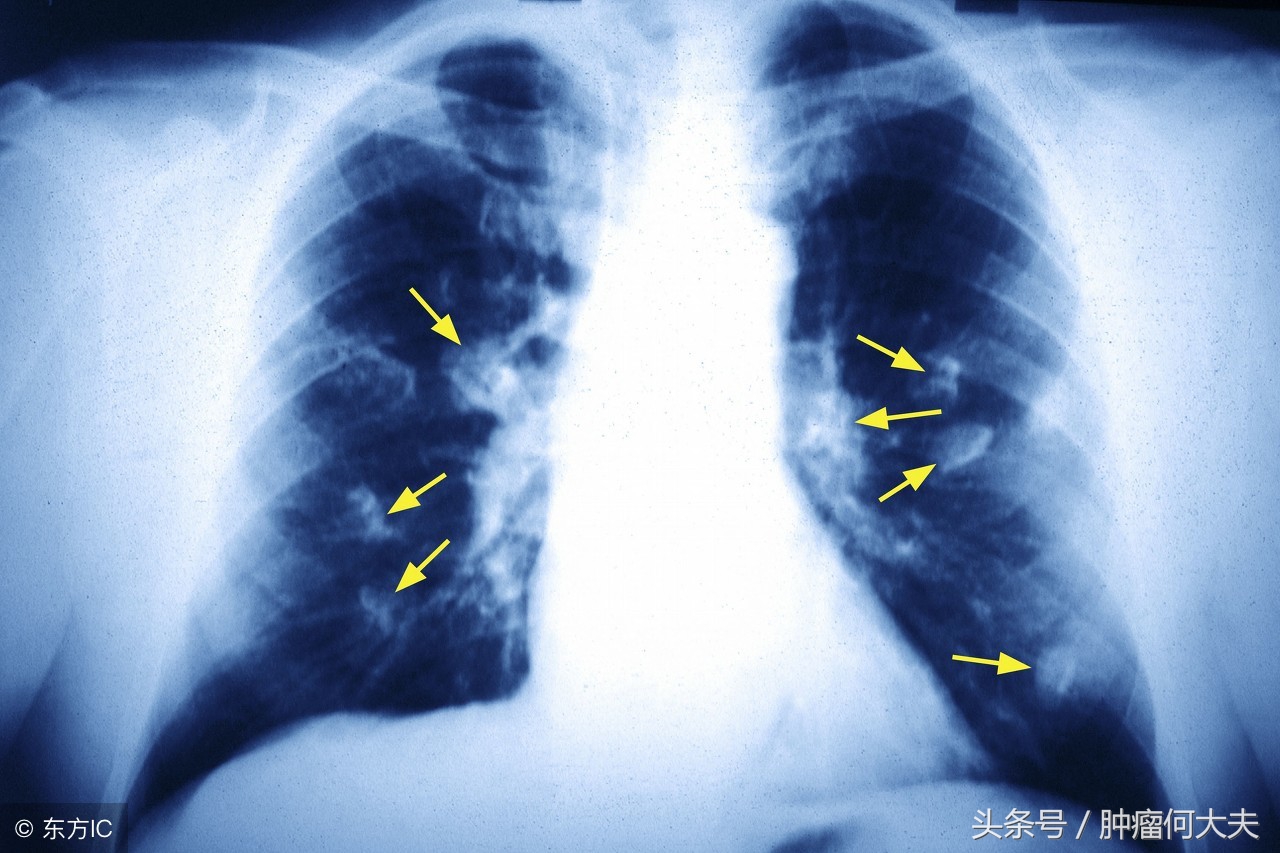

抽一滴血就能检测你患癌与否?两年前,这是一个“白日梦”,但是“今天,我们实际上有数据显示,这对于发现血液中的早期癌症迹象是非常可行的,”美国 Dana-Farber癌症研究所和哈佛医学院Geoffrey R. Oxnard医学博士的一项最新研究结果显示。这项最新研究的中期分析,该研究比较了三种检测方法的性能,以测量超过1000个人中的游离细胞DNA,其中包括150多名肺癌患者。研究发现,无论使用何种检测方法,约有50%的早期肺癌病例都可以检测出来,上升到晚期病例的90%。

研究结果显示,无论使用何种检测方法,在训练集中均检测到41%(29%至54%)的早期肺癌,定义为I至IIIA期。测试集中,检测到50%(29%至71%)的早期肺癌。对于晚期肺癌,定义为IIIB至IV期,测定结果表现较好,90%的病例在测试中得到验证。